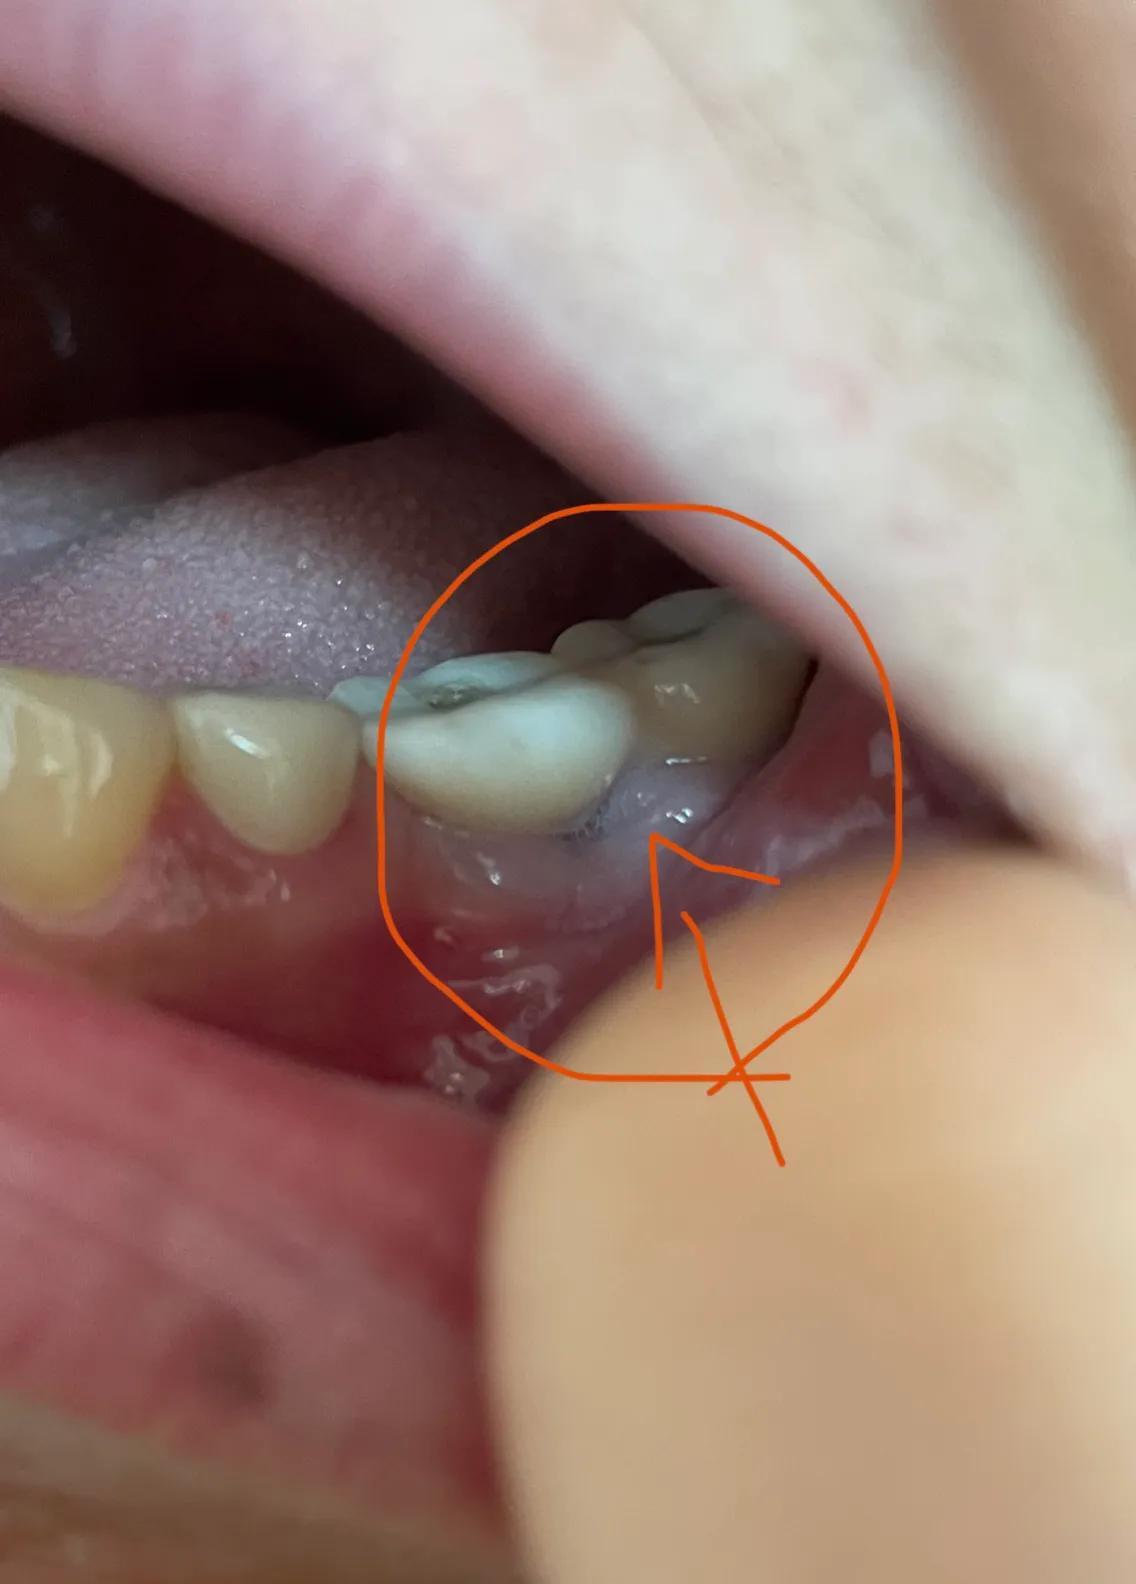

第二副牙帶好 發(fā)現(xiàn)牙齦又缺肉了 更別提貼合牙齒了 而且是一直的疼 一直難受

牙齦是外翻和牙齒分開的 顏色發(fā)白 和其他部位牙齦不是一樣顏色

我不是專業(yè)醫(yī)生 不懂他們所說的正常現(xiàn)象都包括什么 要怎么后期維護(hù) 我現(xiàn)在先不講看不見的難受 疼 先講直觀能看見的 他們哪位醫(yī)生可以做到把大米粒塞到牙齒下面 和將近半厘米的塑料條塞過他們的牙齒 吃過東西就要用沖牙器 不然隔頓就臭了

沒辦法自己又出去拍片子 找原因 看了幾家醫(yī)院 才知道連種植體也種偏了 牙冠也沒有就位………